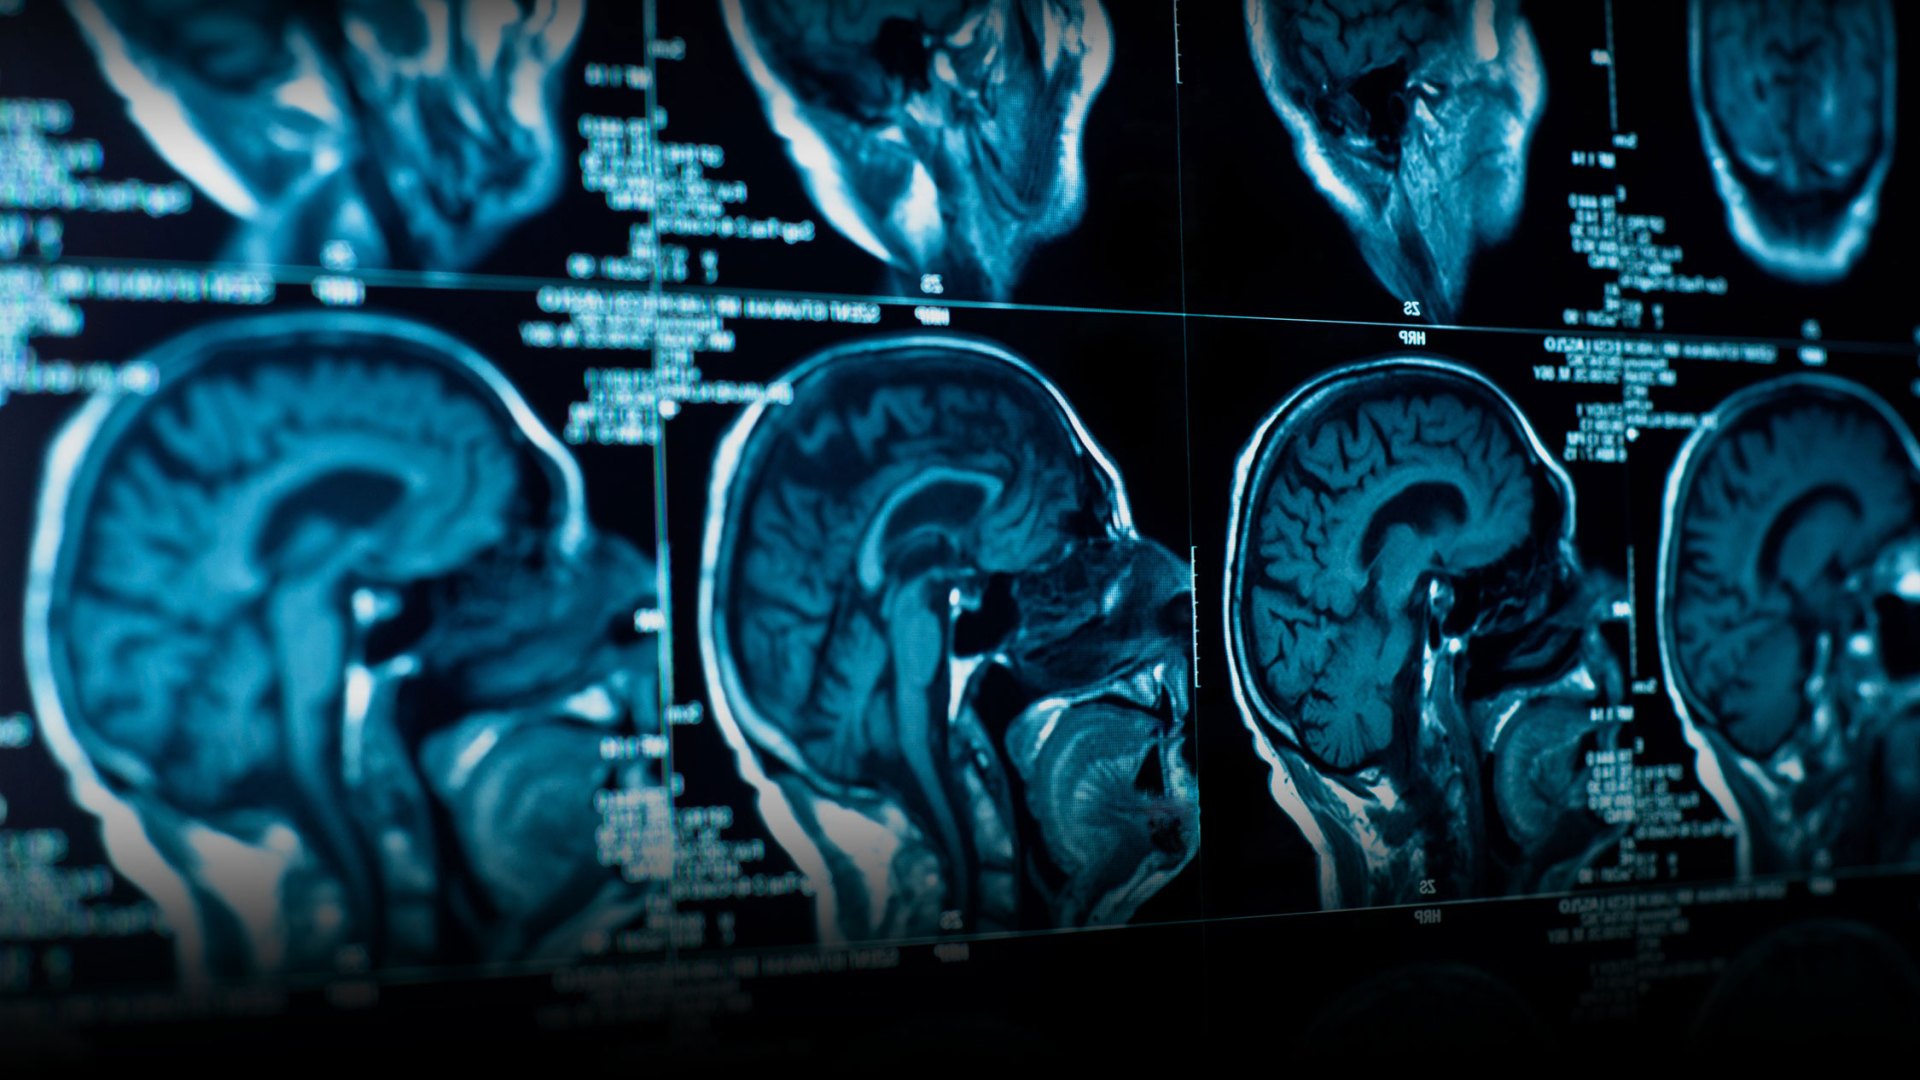

We’re playing with your mind in this issue. Rob Moll’s article discusses how a healthy brain is essential to spiritual growth (and how spiritual disciplines make the brain healthier). Dylan Demarsico tests the logical limits of future and present, time and eternity. And we’ve included “Hurrahing in Harvest” by Gerard Manley Hopkins, a poem perfect for this time of year.

Rob Moll on the brain and spiritual formation, a gospel parable, a Hopkins poem and its analysis.